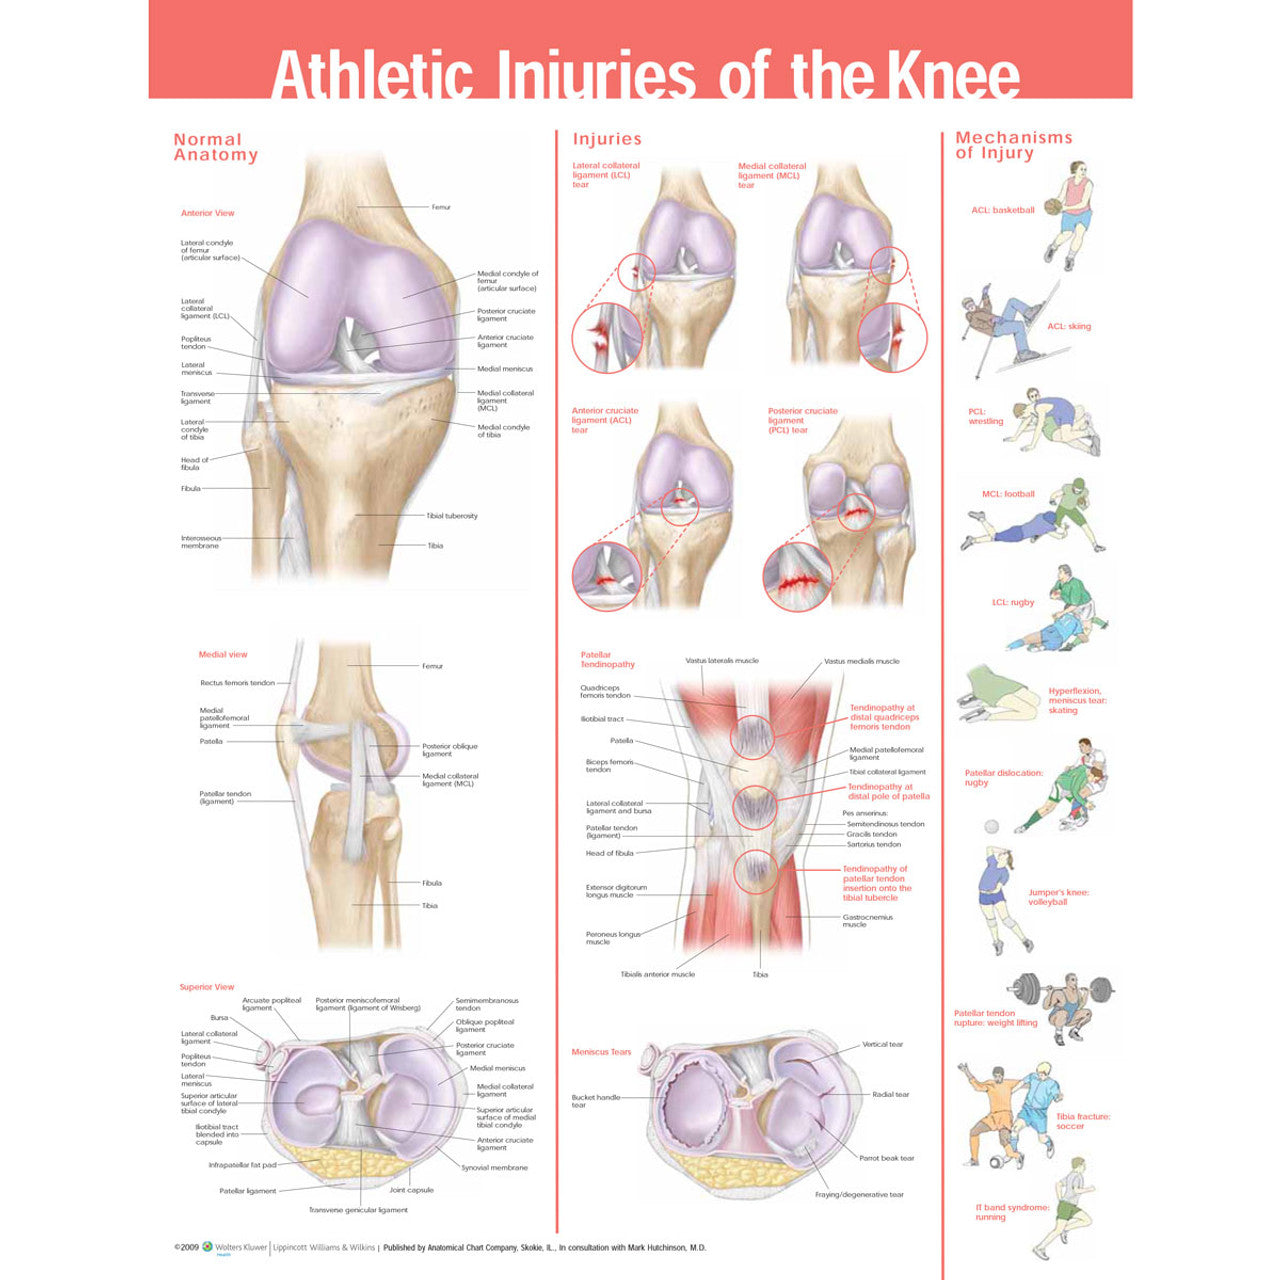

Illustre l’anatomie normale suivante :

- Vue antérieure des os du genou, des ligaments, des tendons, du cartilage

- Vue médiale des os du genou. ligaments, tendons et cartilages

- vue supérieure du genou - os, ligaments, tendons et cartilage

11 images illustrent les mécanismes des blessures au genou dans le contexte d’une figure humaine pratiquant un sport :

- Déchirure du LCA au basket

- Déchirure du LCA en ski

- Déchirure du PCL en lutte

- Déchirure du MCL dans le football

- Déchirure de la LCL au rugby

- hyperflexion/déchirure du ménisque en patinage

- genou du sauteur au volley-ball

- rupture du tendon rotulien en haltérophilie

- fracture du tibia au football

- Syndrome de bande informatique en course à pied.

Les dimensions de ce tableau sont de 20" x 26" (51 cm x 66 cm)